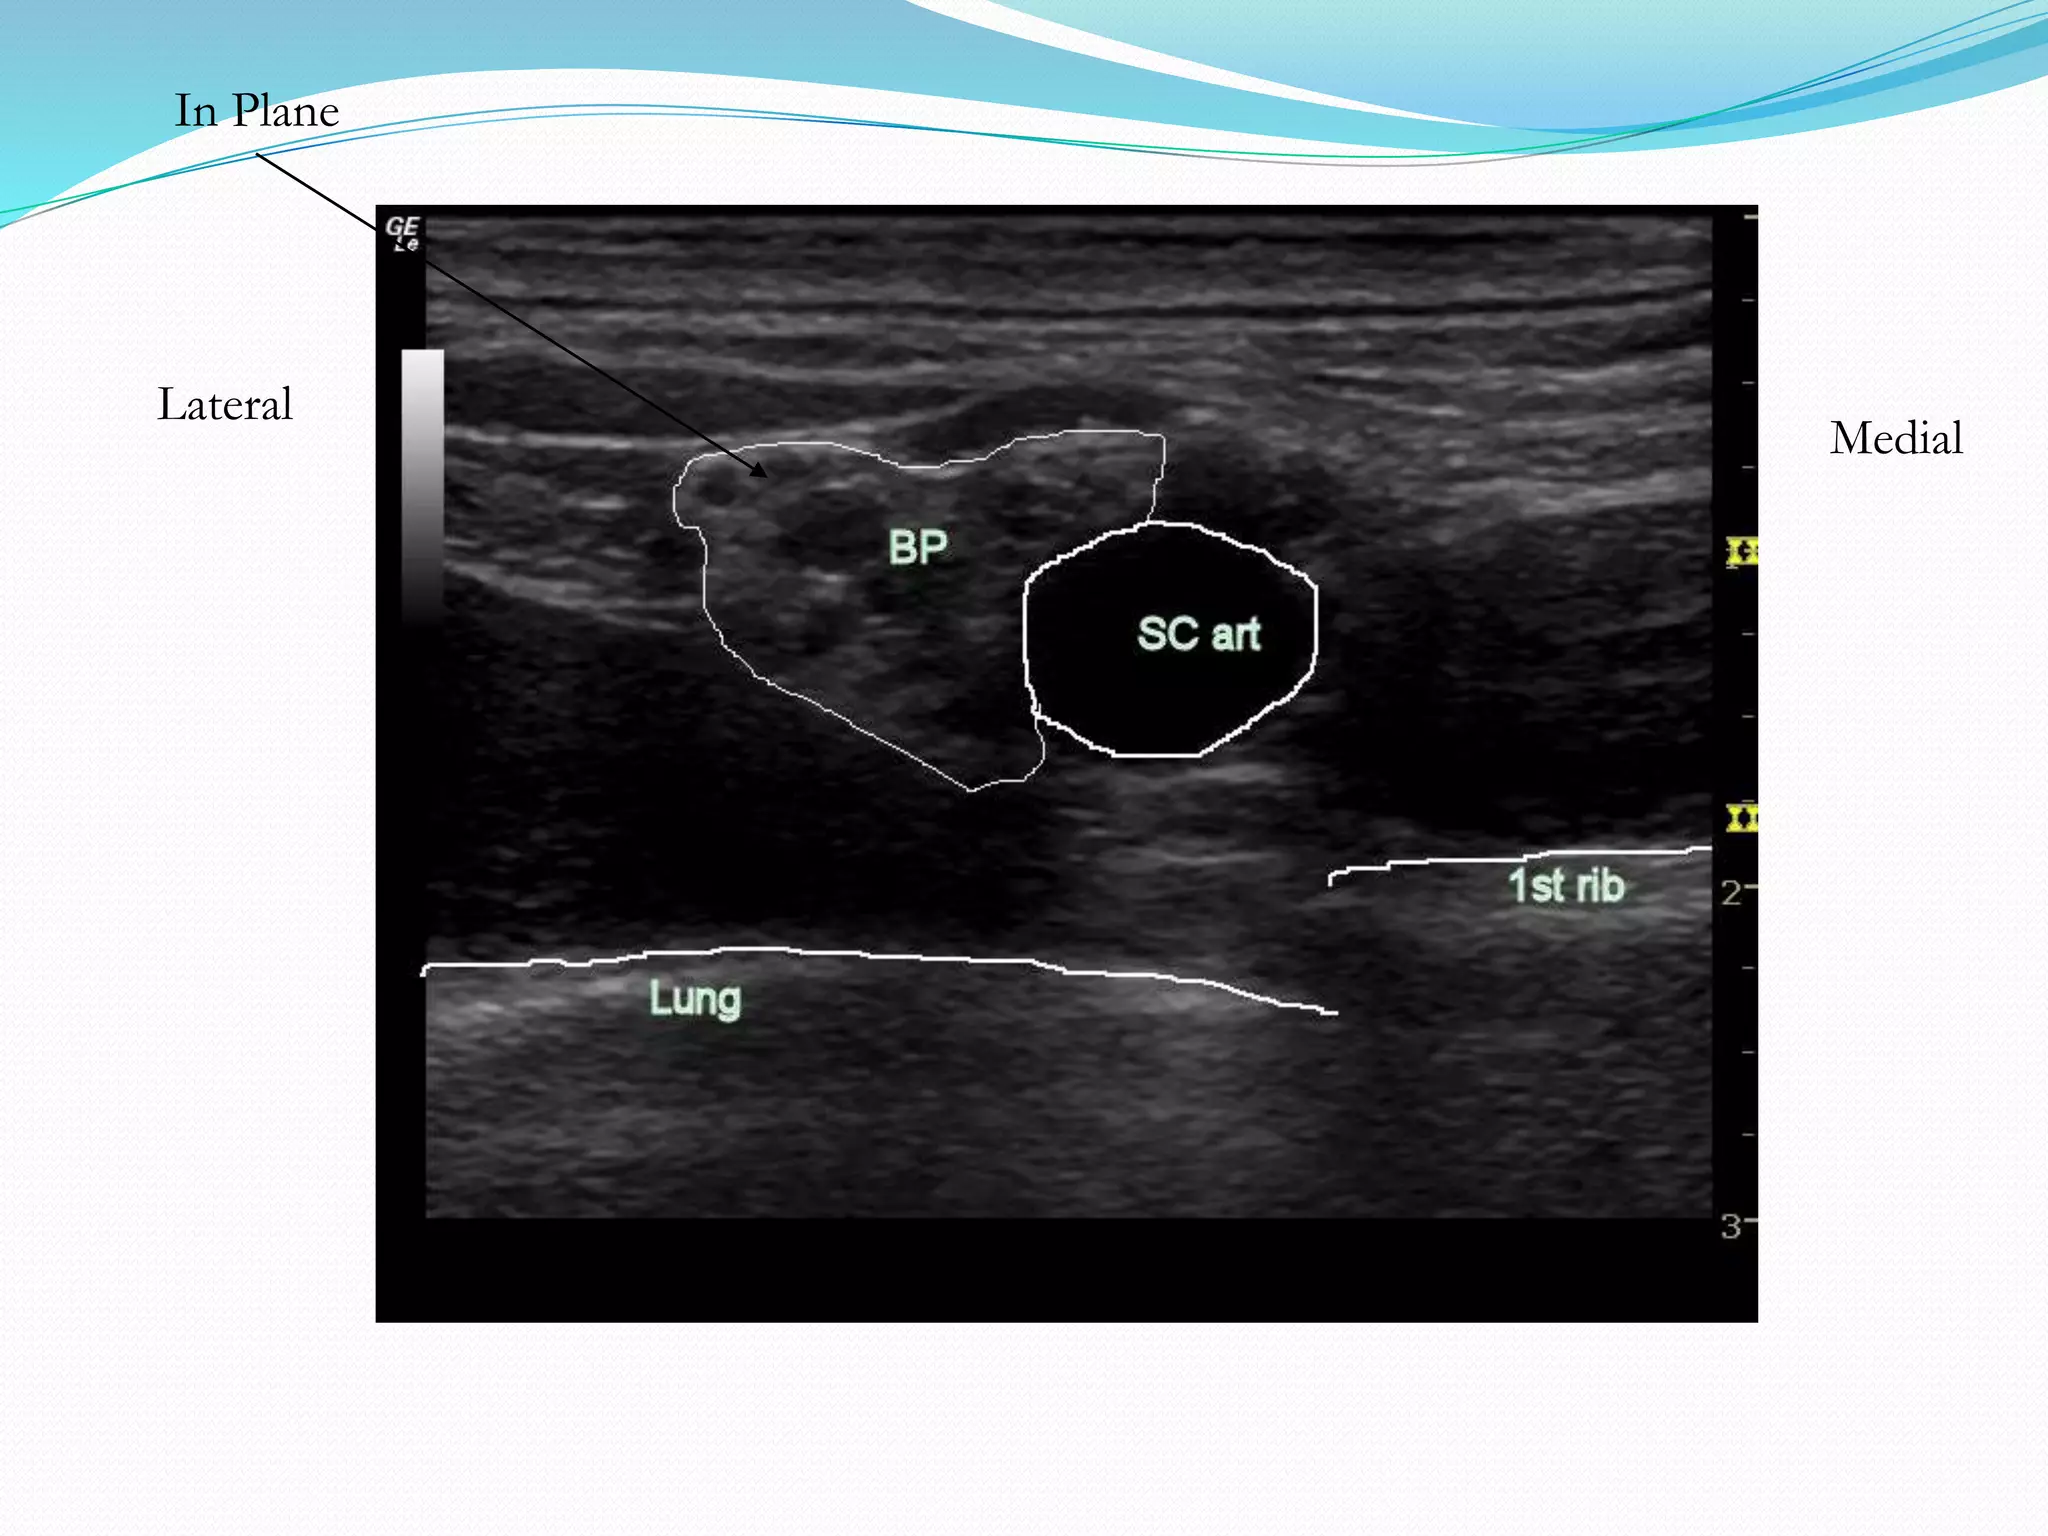

This document provides an overview of brachial plexus anatomy and techniques for brachial plexus nerve blocks. It begins with a description of the brachial plexus formation from cervical and thoracic nerve roots and its branching pattern. Four main approaches for brachial plexus nerve blocks are described: interscalene, supraclavicular, infraclavicular, and axillary. Details are provided on the anatomy and techniques for performing interscalene and supraclavicular brachial plexus blocks. Ultrasound guidance is discussed as an advancement which allows real-time visualization of needle and nerve. Complications are also summarized.